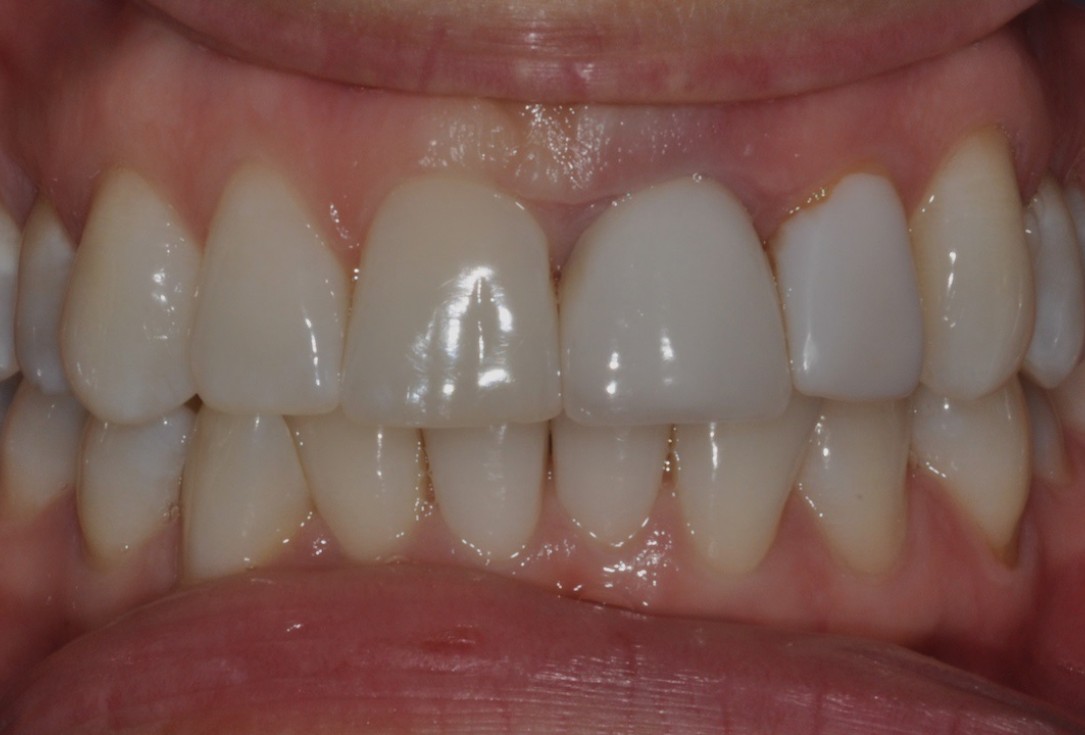

15/16 - Crowns on 21 and 22 in situ

Socket preservation with cerabone® - Dr. R. A. Nader